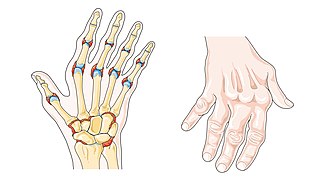

Autoinmunes

O sistema inmunitario ataca aos propios tecidos ou órganos, ou ben non actúa polo que se favorece o desarrollo de enfermidades. Exemplos: esclerose múltiple, esclerose lateral amiotrófica, artrite reumatoide.

Imaxe dunha man con artrite reumatoide

Laboratoires Servier. Artrite reumatoide (Dominio público)

4. Autoinmunes

O sistema inmunitario ataca os propios tecidos ou non actúa correctamente.

Exemplos: Esclerose múltiple, esclerose lateral amiotrófica, artrite reumatoide.